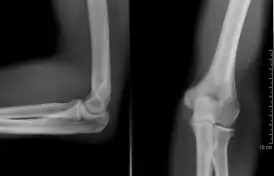

Локтевой сустав

Локтево́й суста́в (лат. articulátio cúbiti) — подвижное соединение плечевой кости (плечо) с локтевой и лучевой костями (предплечье).

По строению локтевой сустав относится (лат. articulatio cubiti) к сложным, поскольку сочленяющиеся кости образуют 3 простых сустава, заключенных в общую капсулу[2]:

- Плечелоктевой (лат. articulatio humeroulnaris)

- Плечелучевой (лат. articulatio humeroradialis)

- Проксимальный лучелоктевой (лат. articulatio radioulnaris proximalis)